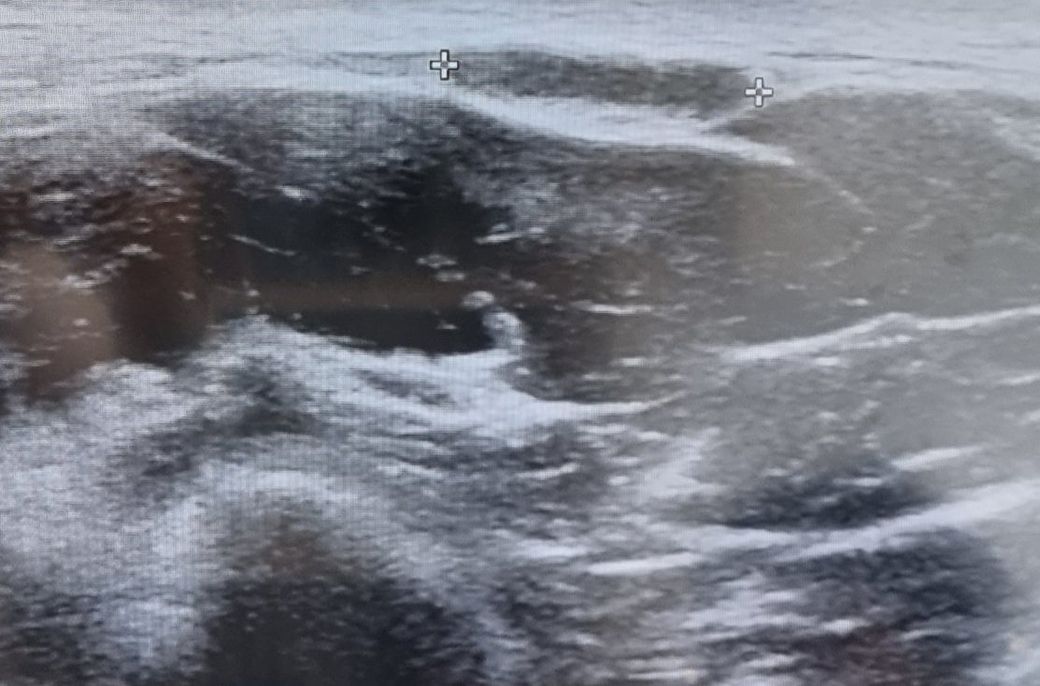

목옆멍울 초음파 좀봐주세용

근육위에 멍울이 저렇게있습니다

1.15cm정도되네요

일반적으로 10년이상 된 종괴가 악성인 경우는 매우 드뭅니다. 또한 초음파상 모양이 불규칙하지 않으므로 악성 가능성은 떨어져 보입니다. 하지만 악성 유무는 조직검사가 가장 정확하므로 의심시에 검사를 받아보시는 것이 좋겠습니다.

연부조직에 오랜기간 존재하는 멍울의 경우 지방종일 가능성이 가장 큽니다. 양성 지방종은 악성으로 잘 변화하지 않고 수십년간 같은 부위에 존재할 수 있습니다. 정확하게 뭔지 알지 위해서는 조직검사를 해야합니다.

• 안타깝지만 초음파 사진의 소견만으로는 그것이 양성인지 악성인지 판별할 수 없습니다. 다만 10년 이상 지속된 점과 생긴 모양이 깔끔한 것을 통해 보았을 때에 악성의 가능성은 매우 낮아 보이므로 너무 걱정하시 않으셔도 될 것 같습니다.

근육 위쪽에 생겨 있어 지방종의 가능성이 높은 것으로 보이며

경계가 명확하고 안쪽으로 음영이 낮은 상태를 유지하고 있어

지방종에 가까운 것으로 보입니다. 크기가 자라지 않는 한 제거

하거나 조직 검사를 하지는 않으며 악성으로 될 확률이 매우

적은 것이 사실입니다.